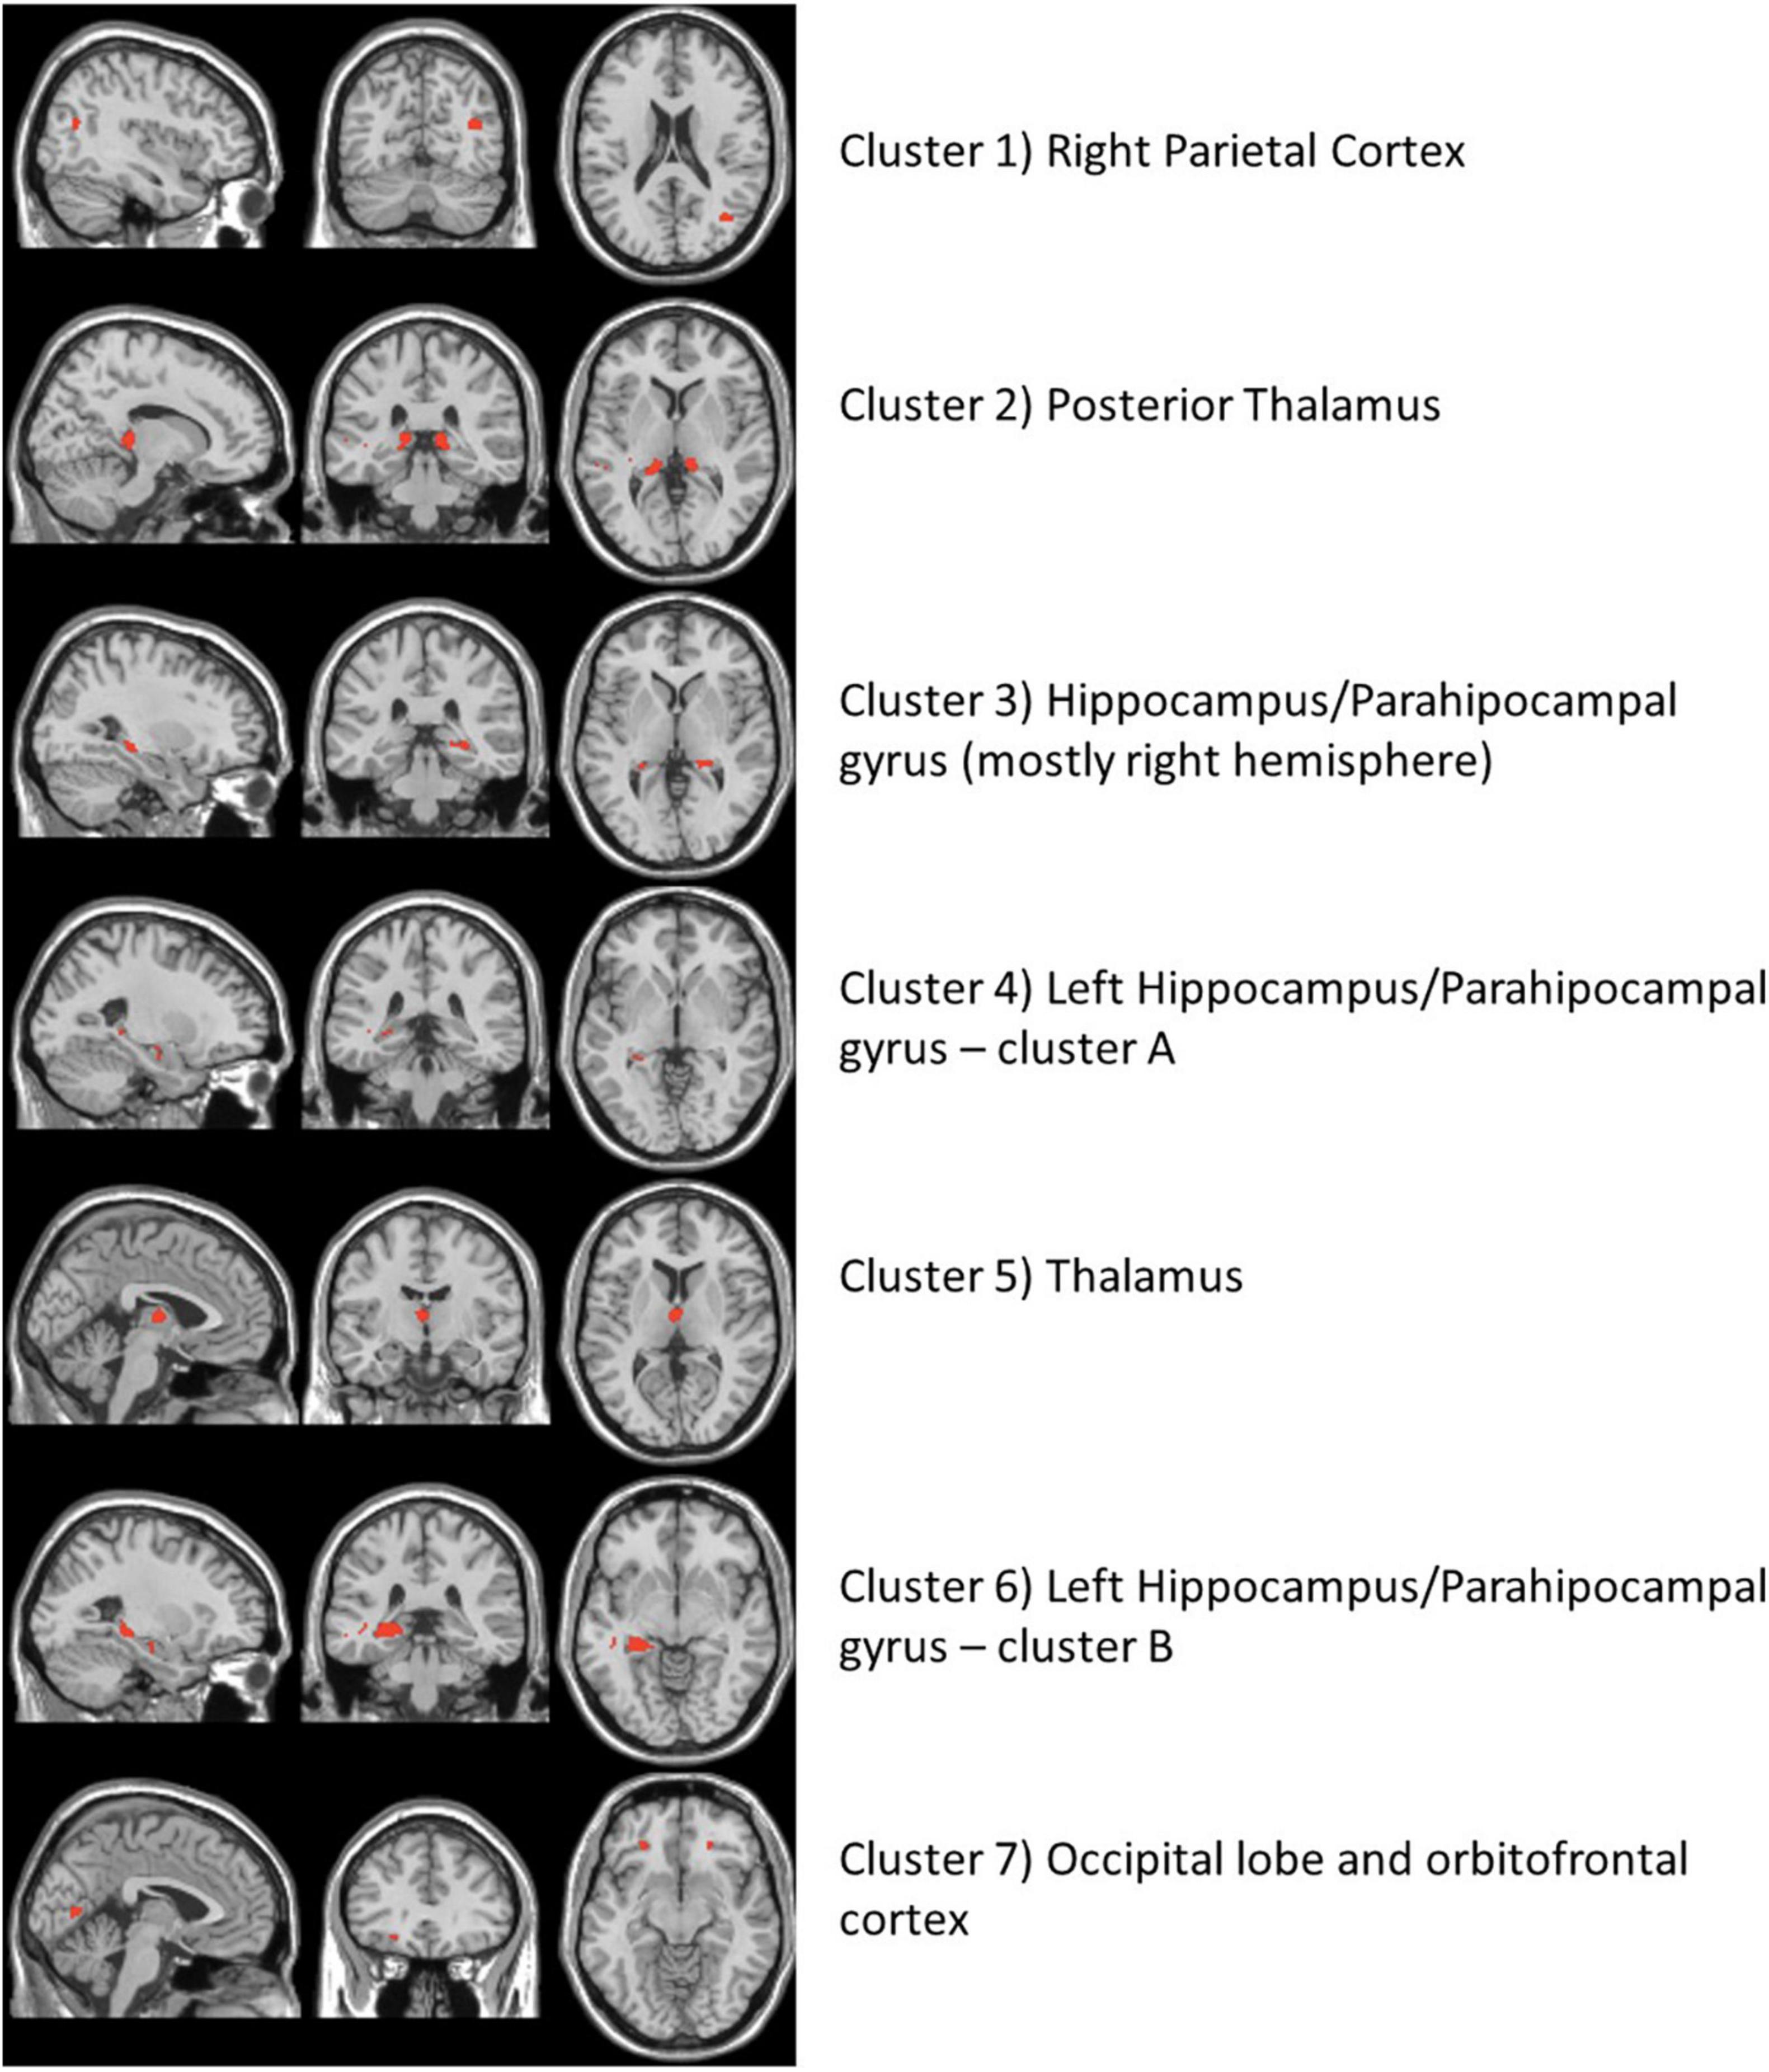

The high-resolution untargeted metabolomics extracted 13,064 unique CSF metabolic features according to mass to charge (m/z) and retention time. After filtering for missing data, 9,804 features remained for all 145 subjects and were used for analysis. The integration of the brain imaging data with the CSF metabolomics data generated twelve unique imaging-metabolite clusters by correlating all 2,375 imaging voxels with 463 of the 9,804 metabolic features (Table 2, Figure 1A, and Supplementary Table 3); 9,341 metabolites did not correlate with an imaging voxel. Seven of those clusters corresponded to contiguous brain regions important to neurocognitive decline: (1) Parietal cortex; (2) Posterior Thalamus; (3) Hippocampus/Parahippocampal gyrus (mostly right hemisphere); (4) Left Hippocampus/Parahippocampal gyrus (cluster A); (5) Thalamus; (6) Left Hippocampus/Parahippocampal gyrus (cluster B); (7) Occipital lobe and orbitofrontal cortex (bilateral) (Figure 2 and Supplementary Figure 4). The remaining five clusters were small (average voxel size = 12.8) and did not conform to contiguous regions of brain in the MNI image and were not further analyzed. The five clusters corresponding to the hippocampus and thalamus shared connections with some of the same metabolites (i.e., hippocampal voxel–metabolite–thalamus voxel correlations). Conversely, the clusters that corresponded to the parietal cortex and the occipital lobe were separate.

Figure 2. The neuroimaging atlas of the seven annotated brain regions as identified by the imaging metabolite clusters from the multiomics network algorithm, xMWAS. The red coloring shows the location of imaging voxels for each cluster.